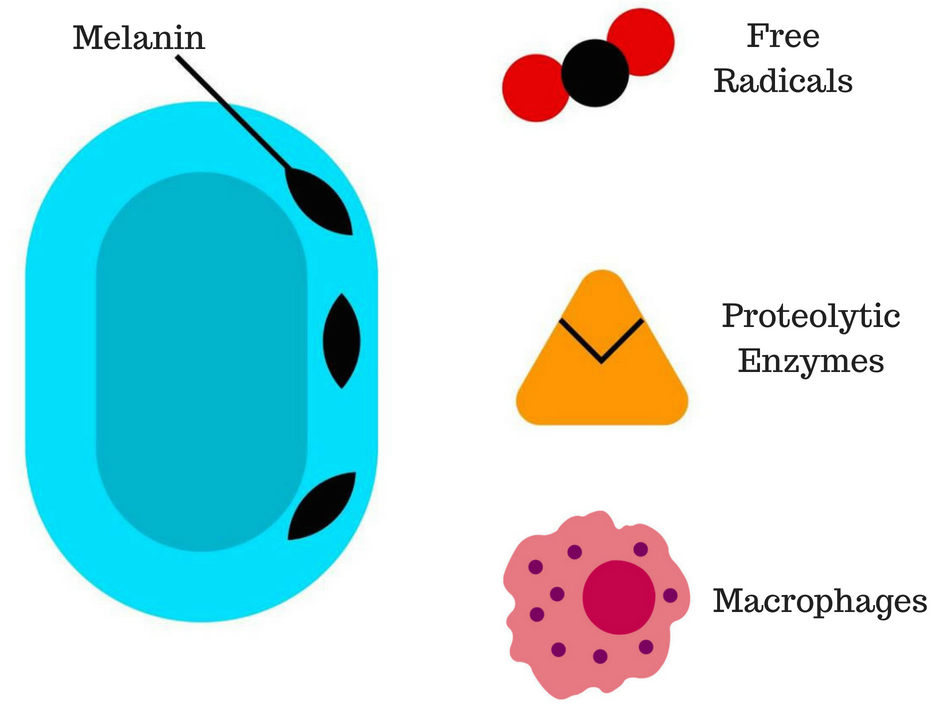

Figure 1: The melanin in the cell wall provides defences against the host immune response.

The mechanism of infection for chromoblastomycosis is traumatic inoculation; once this has occurred, it starts to replicate resulting in muriform cells [2]. Humoral immunity plays a crucial role in the host’s immunological response. Dendritic cells are the first line of defense, followed by neutrophils, macrophages, CD4 and CD8 lymphocytes [5]. Virulence attributes expressed by the fungi include thermotolerance, which allows it to grow at 37 ºC. Also, the fungal cell wall plays a relevant role in the host response [2]. The melanin inclusions provide protection against macrophages, free radicals, such as nitric oxide and proteolytic enzymes [6][7] (Figure 1). However, the mechanisms of host defence and the interaction of these with the pathogen are not yet fully understood [2].